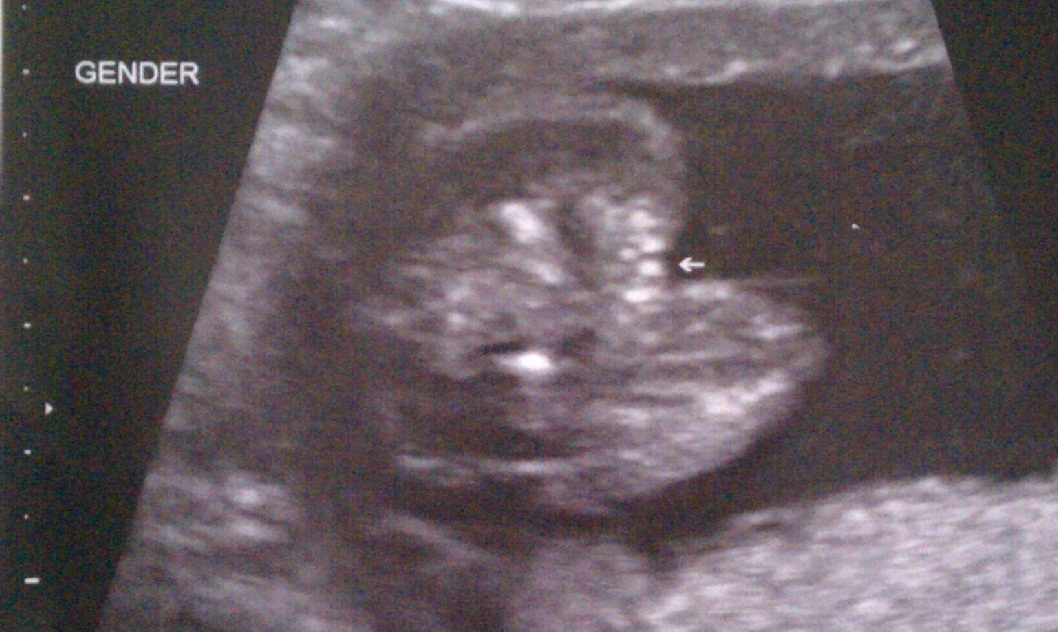

3 Lines (near the arrow) = Girl. 3 Lines (near the arrow) != pumpkin turned on it’s side with part of the bottom missing.